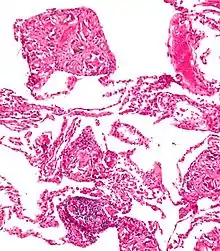

تکهتکههای اجسام خارجی بیشترین موارد ورود جسم خارجی به پوست هستند. عفونت استافیلوکوکوس اورئوس اغلب باعث ایجاد کورک در اطراف آنها میشود.

اجسام خارجی موجود در صفاق در نهایت ممکن است باعث ایجاد گرانولوم جسم خارجی شوند. در موارد بسیار نادر حاملگی خارج رحمی، میتواند منجر به لیتوپدیون شود.